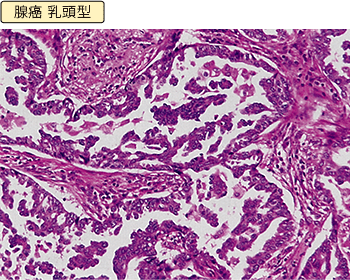

腺がん

唾液の出る唾液腺や胃液の出る胃腺などの腺組織とよく似た形をしているがんのことです。腺がんは、多くの場合、肺の奥のほう(肺野部)の細かく枝分かれした先にできます。女性やタバコを吸わない人にできる肺がんの多くがこの腺がんで、肺がん全体の半数程度を占めます。

肺がんの最終的な判定を行う方法は組織診と細胞診の2種類があります。組織診は検査、あるいは手術でとってきた組織の切れ端をホルマリンで固定し、薄くきった後H-E染色(ヘマトキシリンとエオシンという色素を使うのでこの名前がついています。)して顕微鏡で見ます。細胞の大きさ、形、並び方などを総合的に判定します。別の特殊な染色を使って特定の性質を判断することもあります。